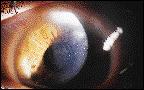

left eye. Visual acuities were OD 20/20 and OS 20/70. Slit lamp examination revealed a

coarse, thickened epithelium, originating at the superior limbus and progressing centrally

in a V-shaped wedge with its apex toward the pupil (Fig. 1). There were no significant

FIG.1: Thickened epithelium shown through slit lamp examination.